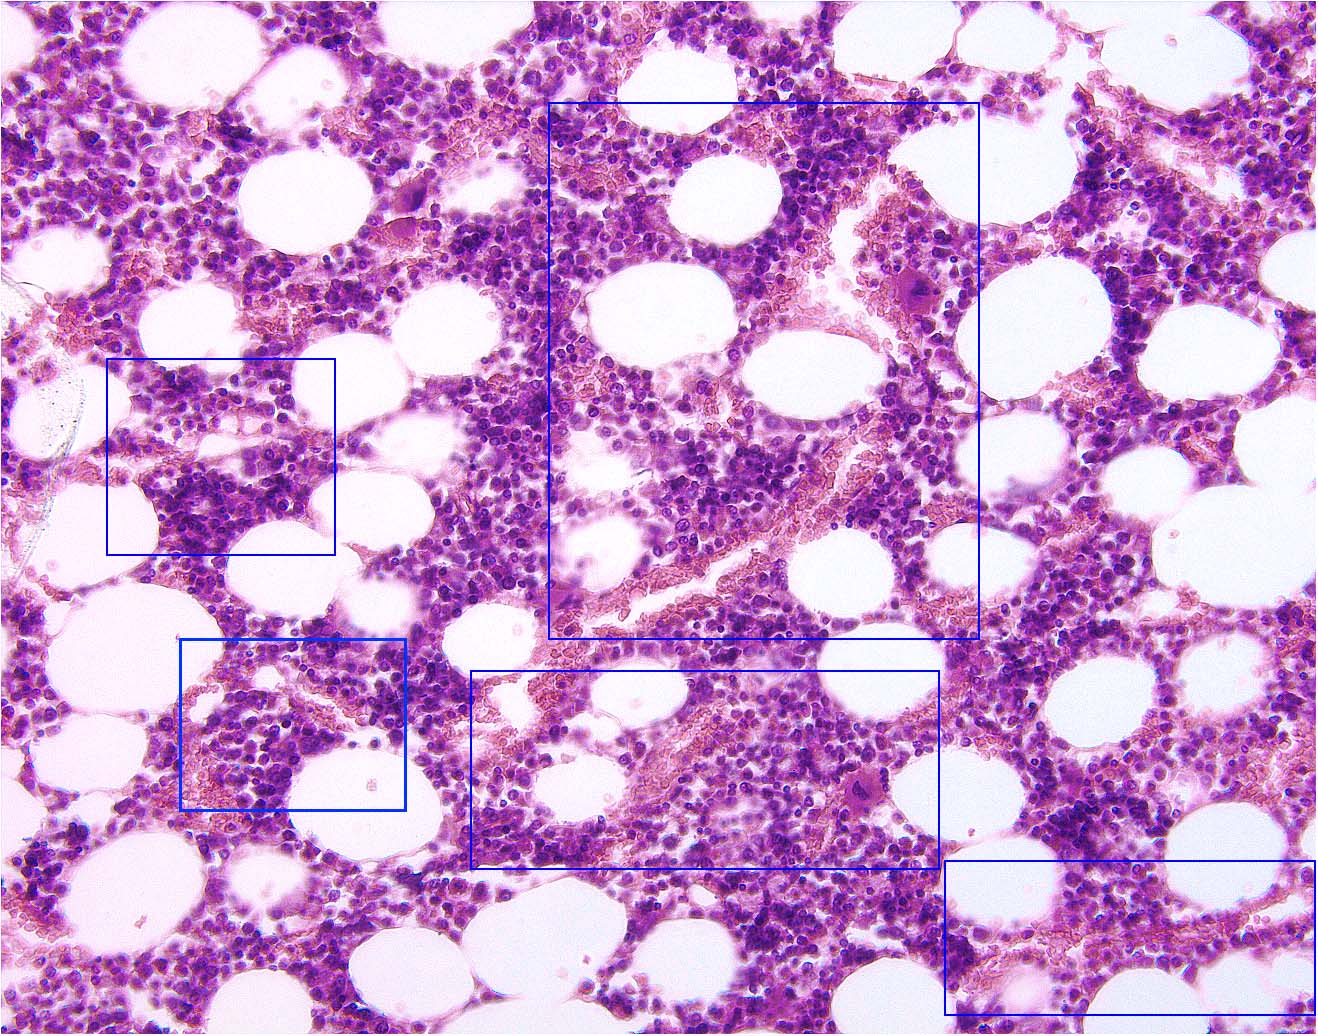

Return to lowest Magnificaiton

Immunology Main Page